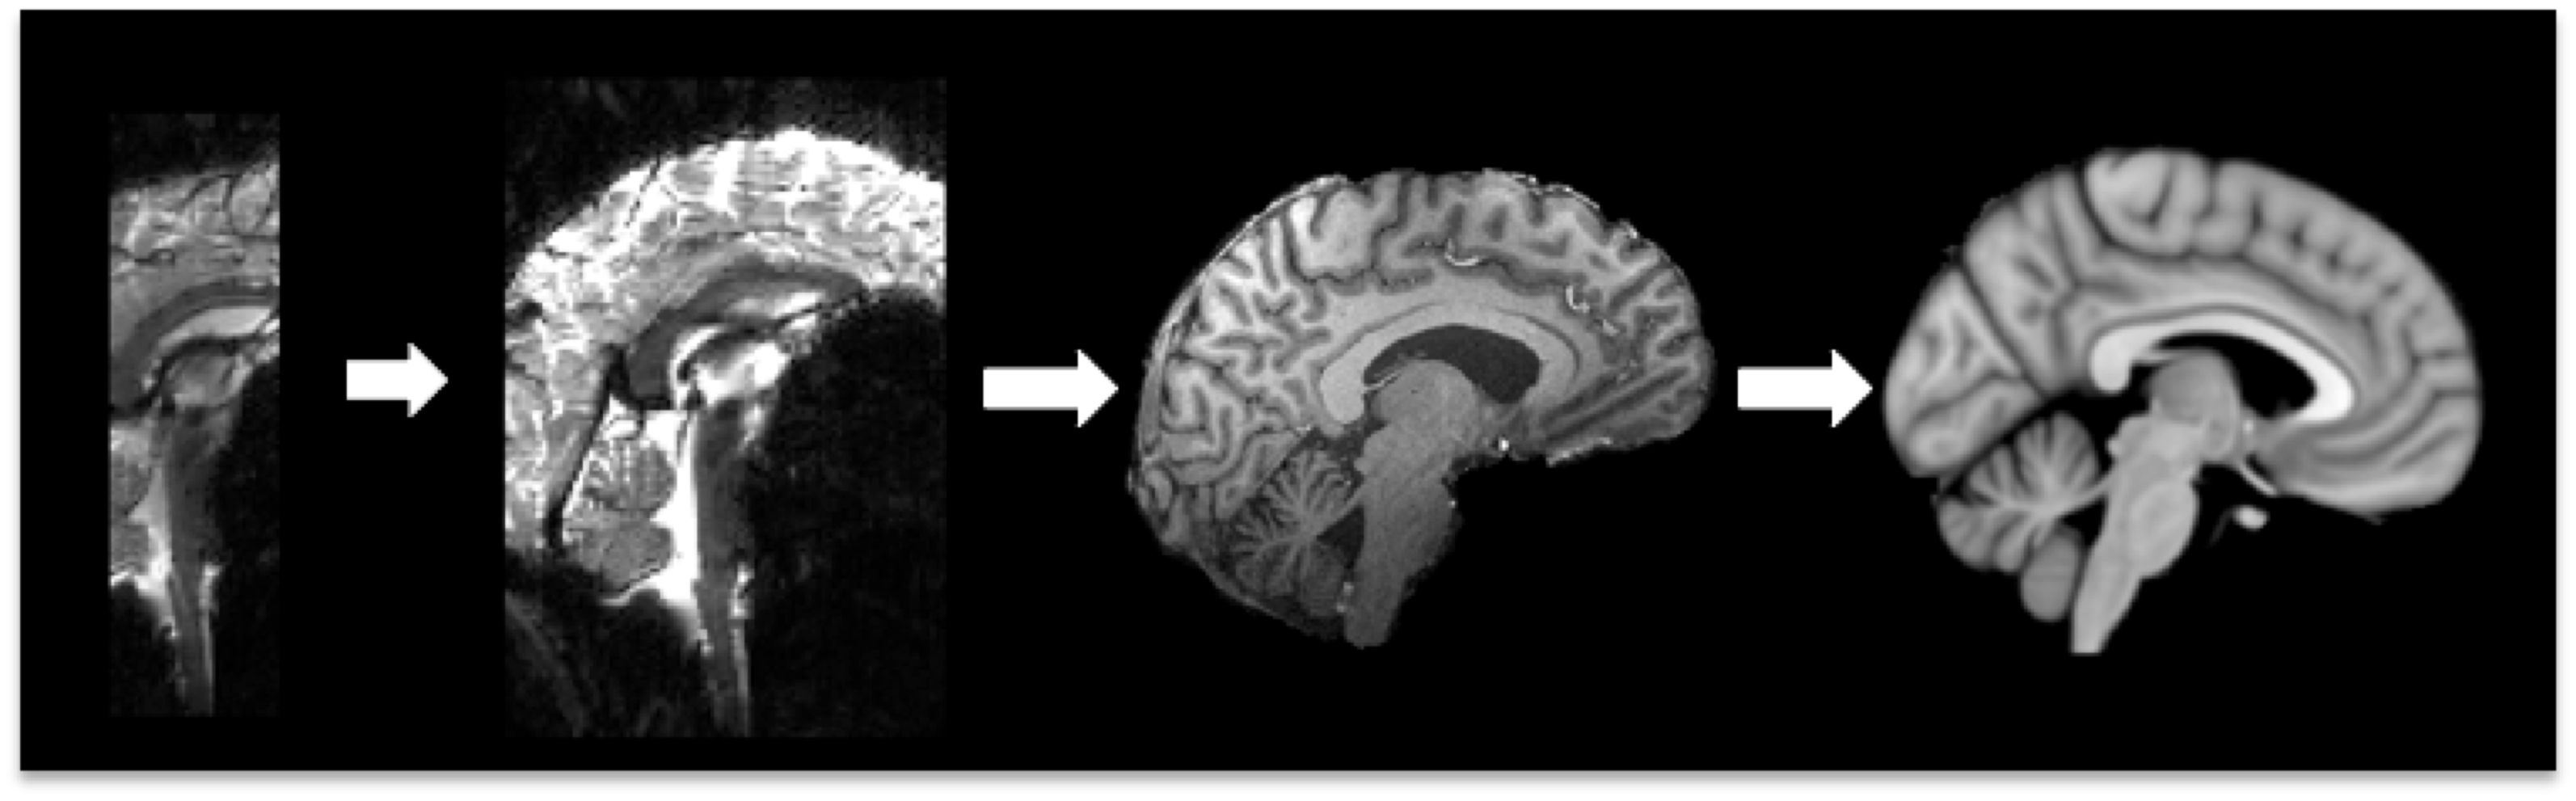

Run brain extraction on the structural image

Structural Registration

- Subject T1 images may need to be registered to either a standard brain or a study template

Registration for structural analysis is within VBM, FreeSurfer and FIRST pathways

Stand-alone registration can be conducted using first linear (FLIRT) followed by non-linear (FNIRT) registration

- First use the FLIRT GUI or terminal command (flirt) with affine registration from structural to standard

- Use the fnirt command line tool, specifying the affine matrix (--aff) and the configuration file (--config=T1_2_MNI152_2mm usually)

Check outputs: Load registration output over the standard brain or study template in FSLView